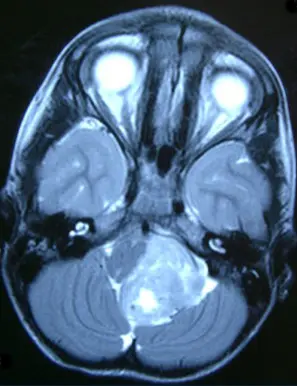

At any age Ependymoma can arise in different compartments of the central nervous system (CNS) including the spine, the cerebellum, and the cortex. These tumors comprise a collection of biologically distinct entities that cannot be reliably distinguished by conventional pathology analysis. It is very likely that only when we account for these different biological entities in clinical trials we will be able to design appropriate treatments for all patients.

In cerebellar ependymoma, groups from Toronto (Michael Taylor), Houston (Ken Aldape) and Heidelberg (Andrey Korshunov, Hendrik Witt and Stefan Pfister) have identified two biologically very distinct disease variants, which typically occur in different ages, and are also associated with different outcome. Furthermore, the researchers could demonstrate that the subtype that appears to behave more aggressive seems to be driven by aberrations in the epigenetic code, information in cells that is transmitted to daughter cells outside of the DNA code. Similar as for cortical ependymomas, this again for the first time offers the possibility for the identification of drugs that directly target this “Achilles’ Heel" of aggressive ependymomas in the cerebellum.